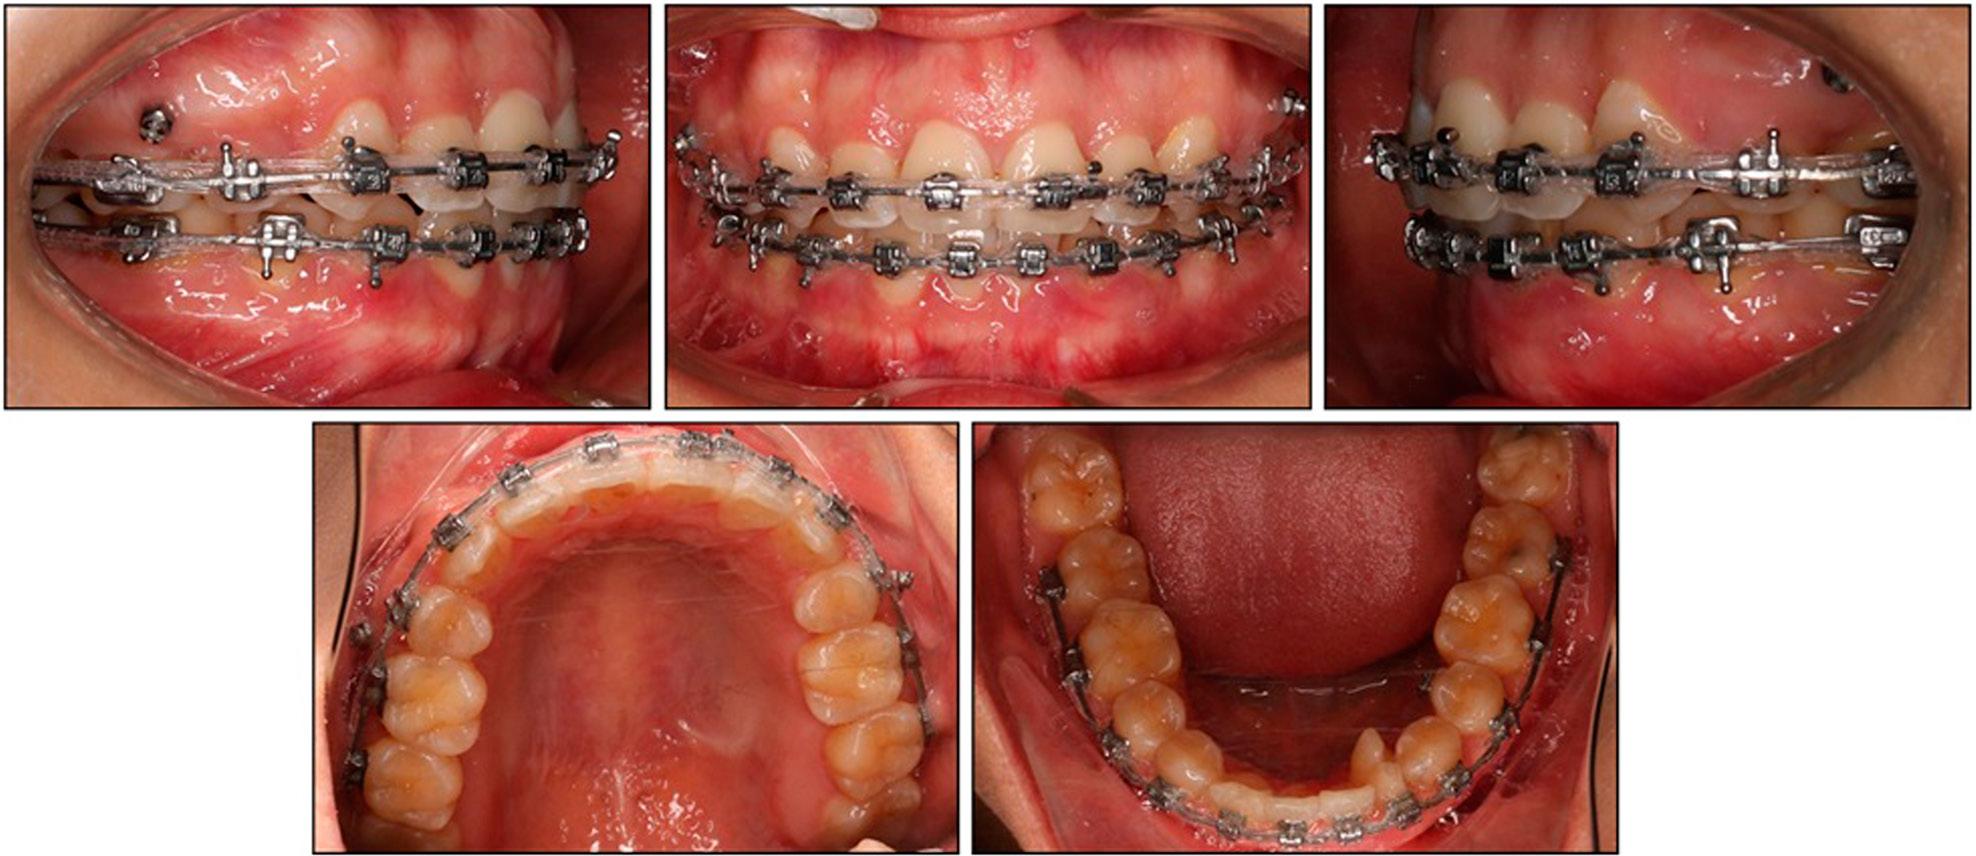

Figure 2.